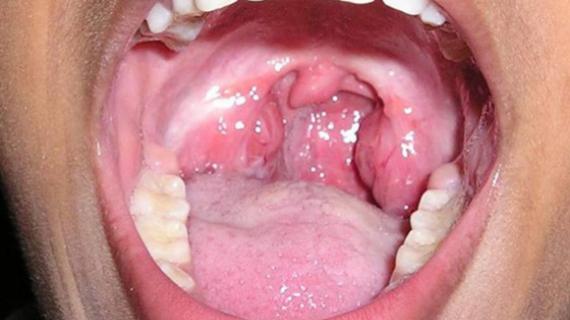

Заболевания горла